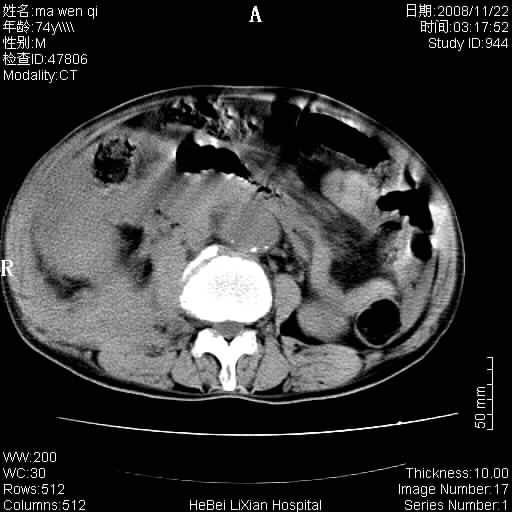

患者男 74岁.突然昏迷,休克6小时.血压70/30,头颅ct未见异常,既往体健.

补充病史,保留导尿10小时,尿袋内只有少许尿液,患者于住院后15小时后去世.

腹主动脉、双侧髂动脉夹层动脉瘤破裂出血进入腹腔。

1)考虑双侧髂动脉瘤并右侧动脉瘤破裂出血,右侧腹膜后及腹腔积血。2)双侧腹股沟疝。

1)考虑,腹主动脉、双侧髂动脉夹层动脉瘤破裂伴右侧腹膜后及腹腔积血。2)双侧腹股沟疝。

1)考虑胸、腹主动脉、双侧髂动脉瘤并右侧动脉瘤破裂出血,右侧腹膜后及腹腔积血。2)双侧腹股沟疝。